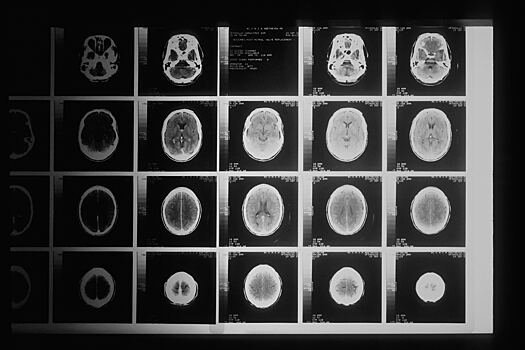

У 80-летней жительницы Сахалина во время компьютерной томографии была обнаружена трехсантиметровая игла, вонзившаяся в мозг. Об этом пишет РИА Новости со ссылкой на Telegram-канал регионального Министерства здравохранения.

По данным ведомства, игла оказалась проникла в левую теменную долю при рождении, но на самочувствии ребенка это никак не сказалось, прием даже головные боли не мучили женщину в течение всей жизни.

Также сообщается, то в настоящее время женщина находится под наблюдением врачей, ее жизнь и здоровье вне опасности. Иглу решено не извлекать, чтобы не ухудшить состояние.